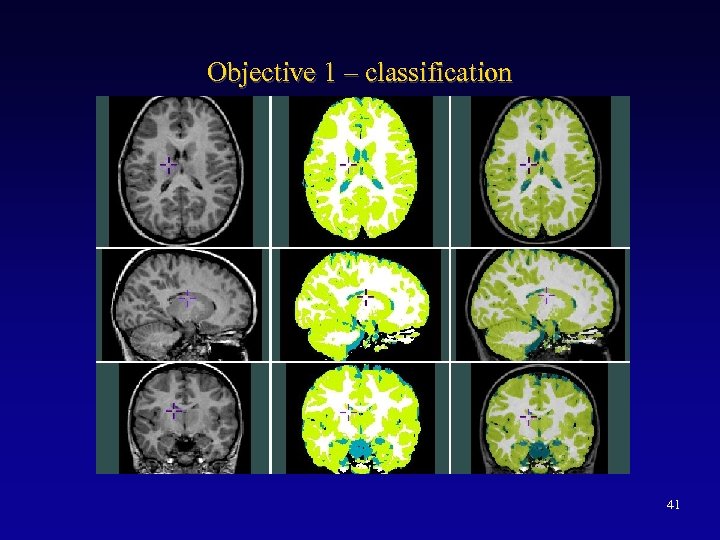

INSECT ANIMAL ASP SEAL Manual 40 Auto

Objective 1 – classification 41

Obj 1 – Tissue SPAMs (n=337) 42